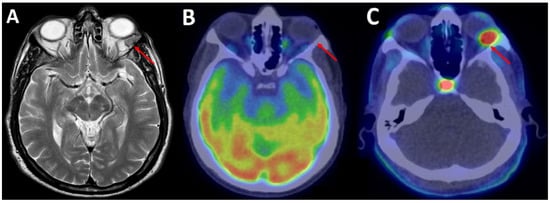

| 9 | Sardaro et al. [7] | 2021 | 69, M | Left orbit | / | 18F-FDG | Absent |

| 18F-FCH | Intense, SUVmax 6.8 | ||||||